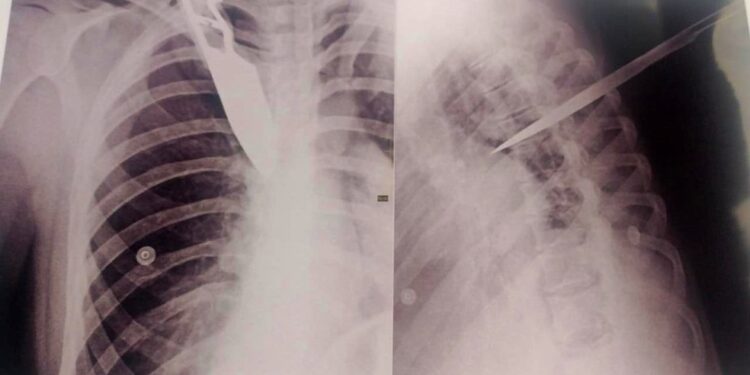

GÁLIA (SP) – A imagem de um raio-x com uma faca cravada nas costas chocou as pessoas que souberam o que aconteceu com uma mulher de 33 anos, em Marília, São Paulo (SP). A vítima, de acordo com a polícia, era a ex-mulher de um detento e a tentativa de homicídio aconteceu durante uma discussão, na terça-feira (28).